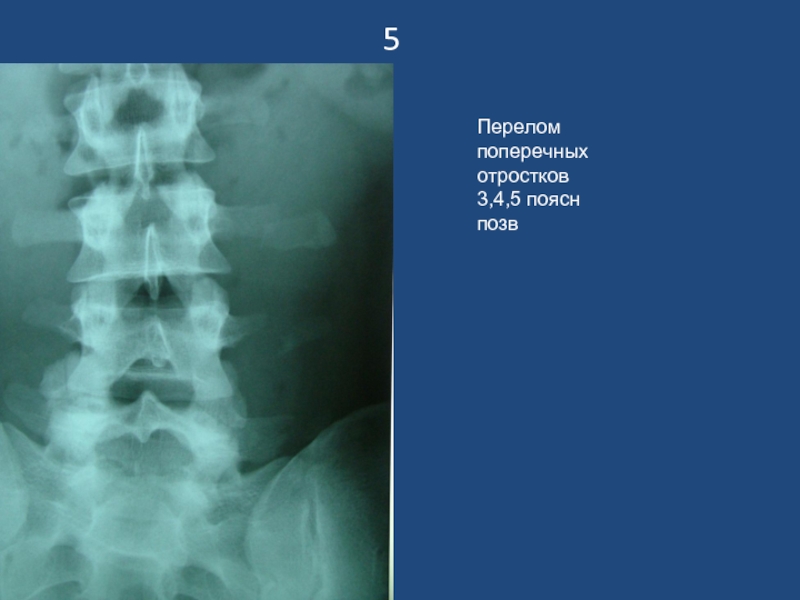

Слайд 65

Перелом поперечных отростков 3,4,5 поясн позв